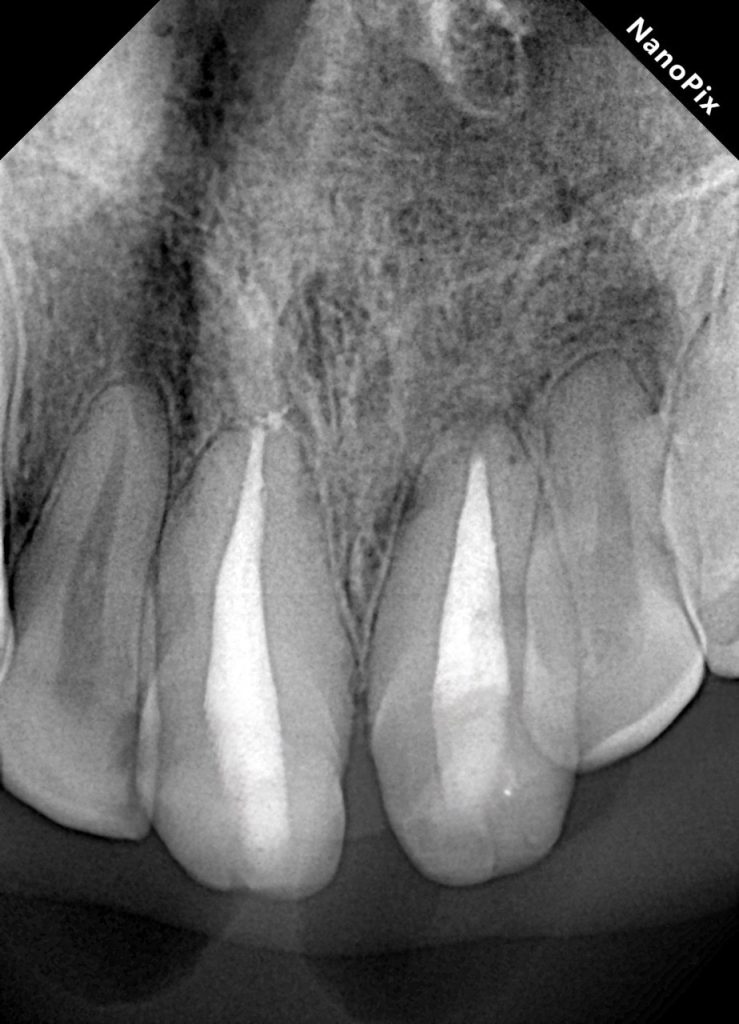

Post-operative radiographs showed a dense, continuous obturation with ideal apical termination and restoration of periapical bone architecture at 6-month follow-up (Fig 11-12).